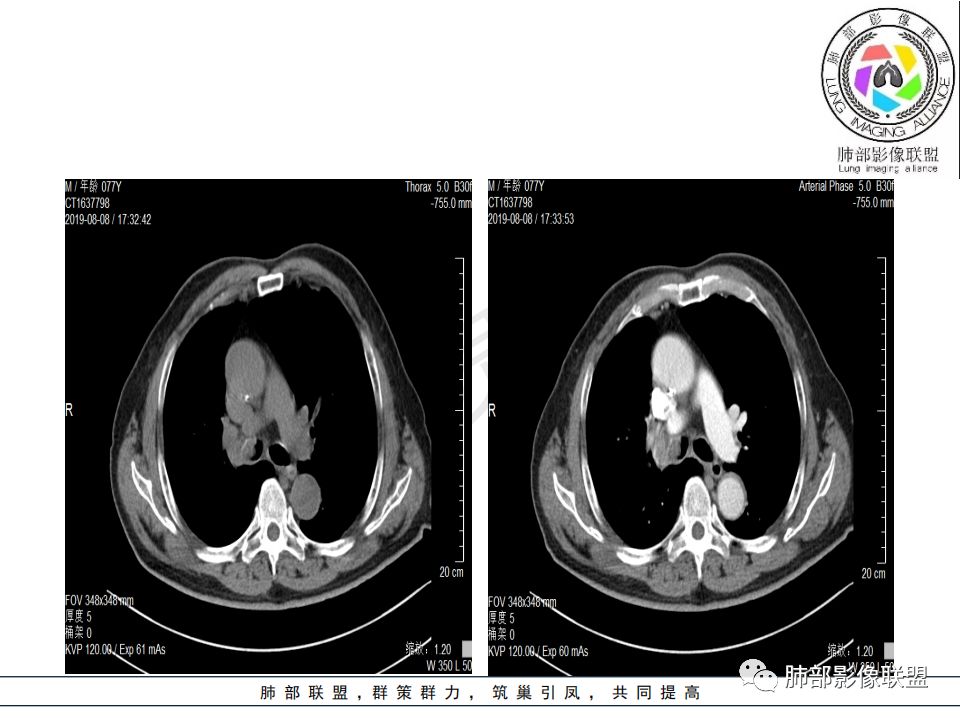

病史:男.77岁,咳嗽1月;干咳,少许白痰,无发热,2013胃癌术后,角蛋白24.65(0-3.07),SCC和proGRP不高;

影像:影像右侧大支气管阻塞,临床没有症状或很轻微,要想到胃腺癌转移;胸壁代偿好,透亮度稍低不明显,慢性过程;34.8-52.5HU,主病灶支气管前壁另有1结节,都做成增强两期了,动脉期较平扫有强化;

诊断:多发,转移,无淋巴结及胸腔积液;

鉴别:原发鳞癌。

晨读:患者老年男性,以咳嗽一月就诊,少量白痰,胸CT:纵隔右移,右肺体积缩小,气管下段管壁可见结节样改变,气管软骨变形,气管下段及右主支气管可见新生物向管壁浸润,并向管腔外生长,右上肺肺不张,但不张边缘可见病灶呈膨胀性生长,可见分叶,增强后强化明显。考虑:肺部恶性病变(鳞癌?)

右肺上叶肿块,边缘光滑,略膨隆,近段支气管堵塞,平扫密度均匀,增强后不均匀强化,其内可见不规则血管和坏死,纵隔淋巴结肿大,老年男性,无感染性病史,综合考虑恶性肿瘤(鳞癌,腺癌),鉴别:OP(一般下叶多见)